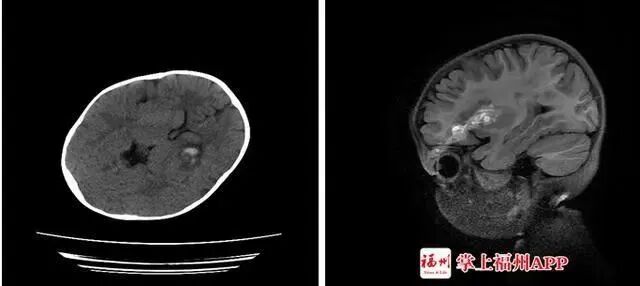

开放性颅脑损伤、颅内少量血肿、左眼眶上壁骨折伴左眼眶周围软组织挫裂伤。虽然脑脊液没有漏出的现象,情况不算太糟糕,但也难以保证她的后期视力不会受到影响。

图源于 | 掌上福州APP

这支与筷子粗细无异的棍,直接插入颅内,导致颅内出血。